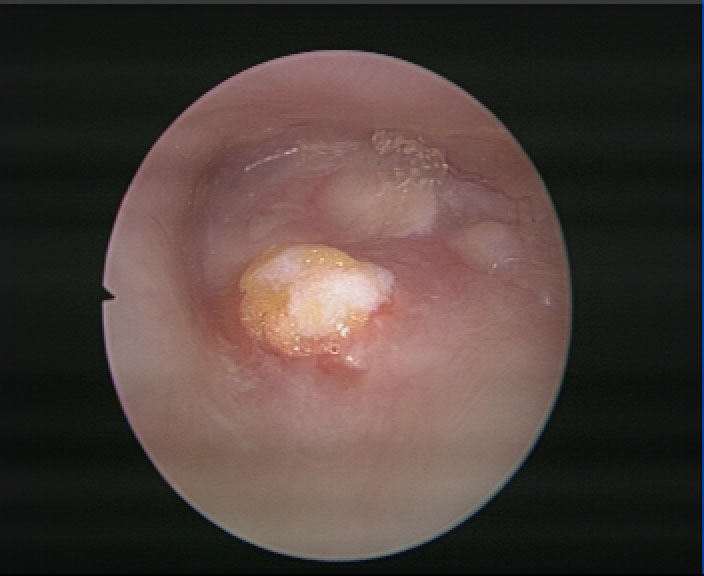

中耳炎鼓膜穿孔

中耳炎使鼓膜穿孔